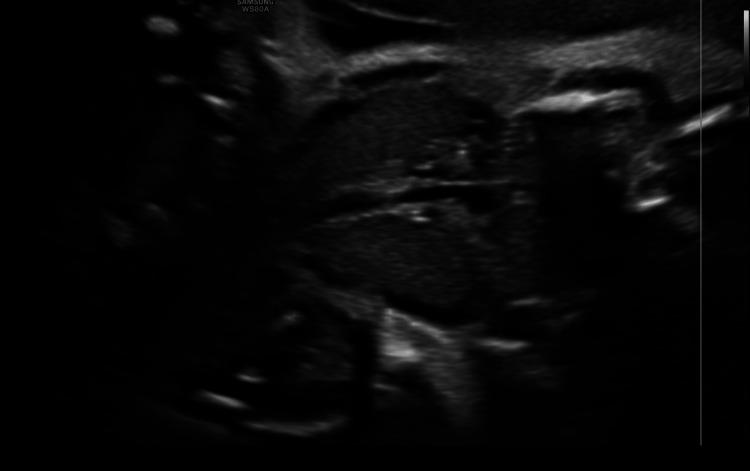

甲状腺功能正常的患者诊断出胎儿甲状腺肿:胎儿甲状腺疾病的一种罕见表现

Fetal Goiter Diagnosed in a Euthyroid Patient: An Unusual Presentation of the Fetal Thyroid Disease.

Fetal thyroid disease is rare, and the disease is mostly contextualized in the setting of a treated maternal thyroid disease. The presentation of thyroid disease in the fetus of a euthyroid mother is unusual. This paper presents the case of a 21-week pregnant woman with an incidental finding from a detailed anatomy ultrasound and evaluates available diagnostic and therapeutic management options. There is no consensus with sufficient evidence given the unusual presentation of this type of pathology. In most cases, the evidence is in the etiology of a mother with previous thyroid pathology that modifies the fetal outcome. Hence, it is important to describe cases to accumulate and, at some point, sufficient evidence of different treatments, with the intention of improving the quality of the recommendations. The management of fetal euthyroid goiter is a complex challenge. Most specialists manage the information on a case-by-case basis, with the same general goals as in patients with other thyroid pathologies.

摘要

胎儿甲状腺疾病较为罕见,且该疾病大多与已接受治疗的母体甲状腺疾病相关。甲状腺功能正常的母亲所怀胎儿出现甲状腺疾病的情况并不常见。本文介绍了一名21周孕妇的病例,该孕妇在详细的解剖超声检查中意外发现相关情况,并评估了现有的诊断和治疗管理方案。鉴于这类病理情况的不寻常表现,目前尚无足够证据支持的共识。在大多数情况下,证据存在于有既往甲状腺病理情况的母亲的病因中,这会改变胎儿的结局。因此,描述病例以积累不同治疗方法的充分证据很重要,目的是提高建议的质量。胎儿甲状腺功能正常的甲状腺肿的管理是一项复杂的挑战。大多数专家逐案处理信息,其总体目标与其他甲状腺疾病患者相同。